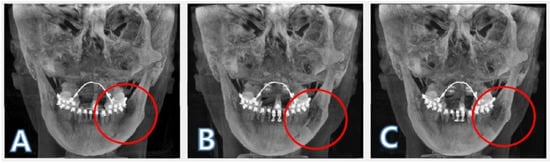

2.5. ROI Image Acquisition and Boundary Separation

2.6. ROI Volume and Mean Pixel Value Calculation

3.1. Bone Volume Change

3.2. Pixel Value Change